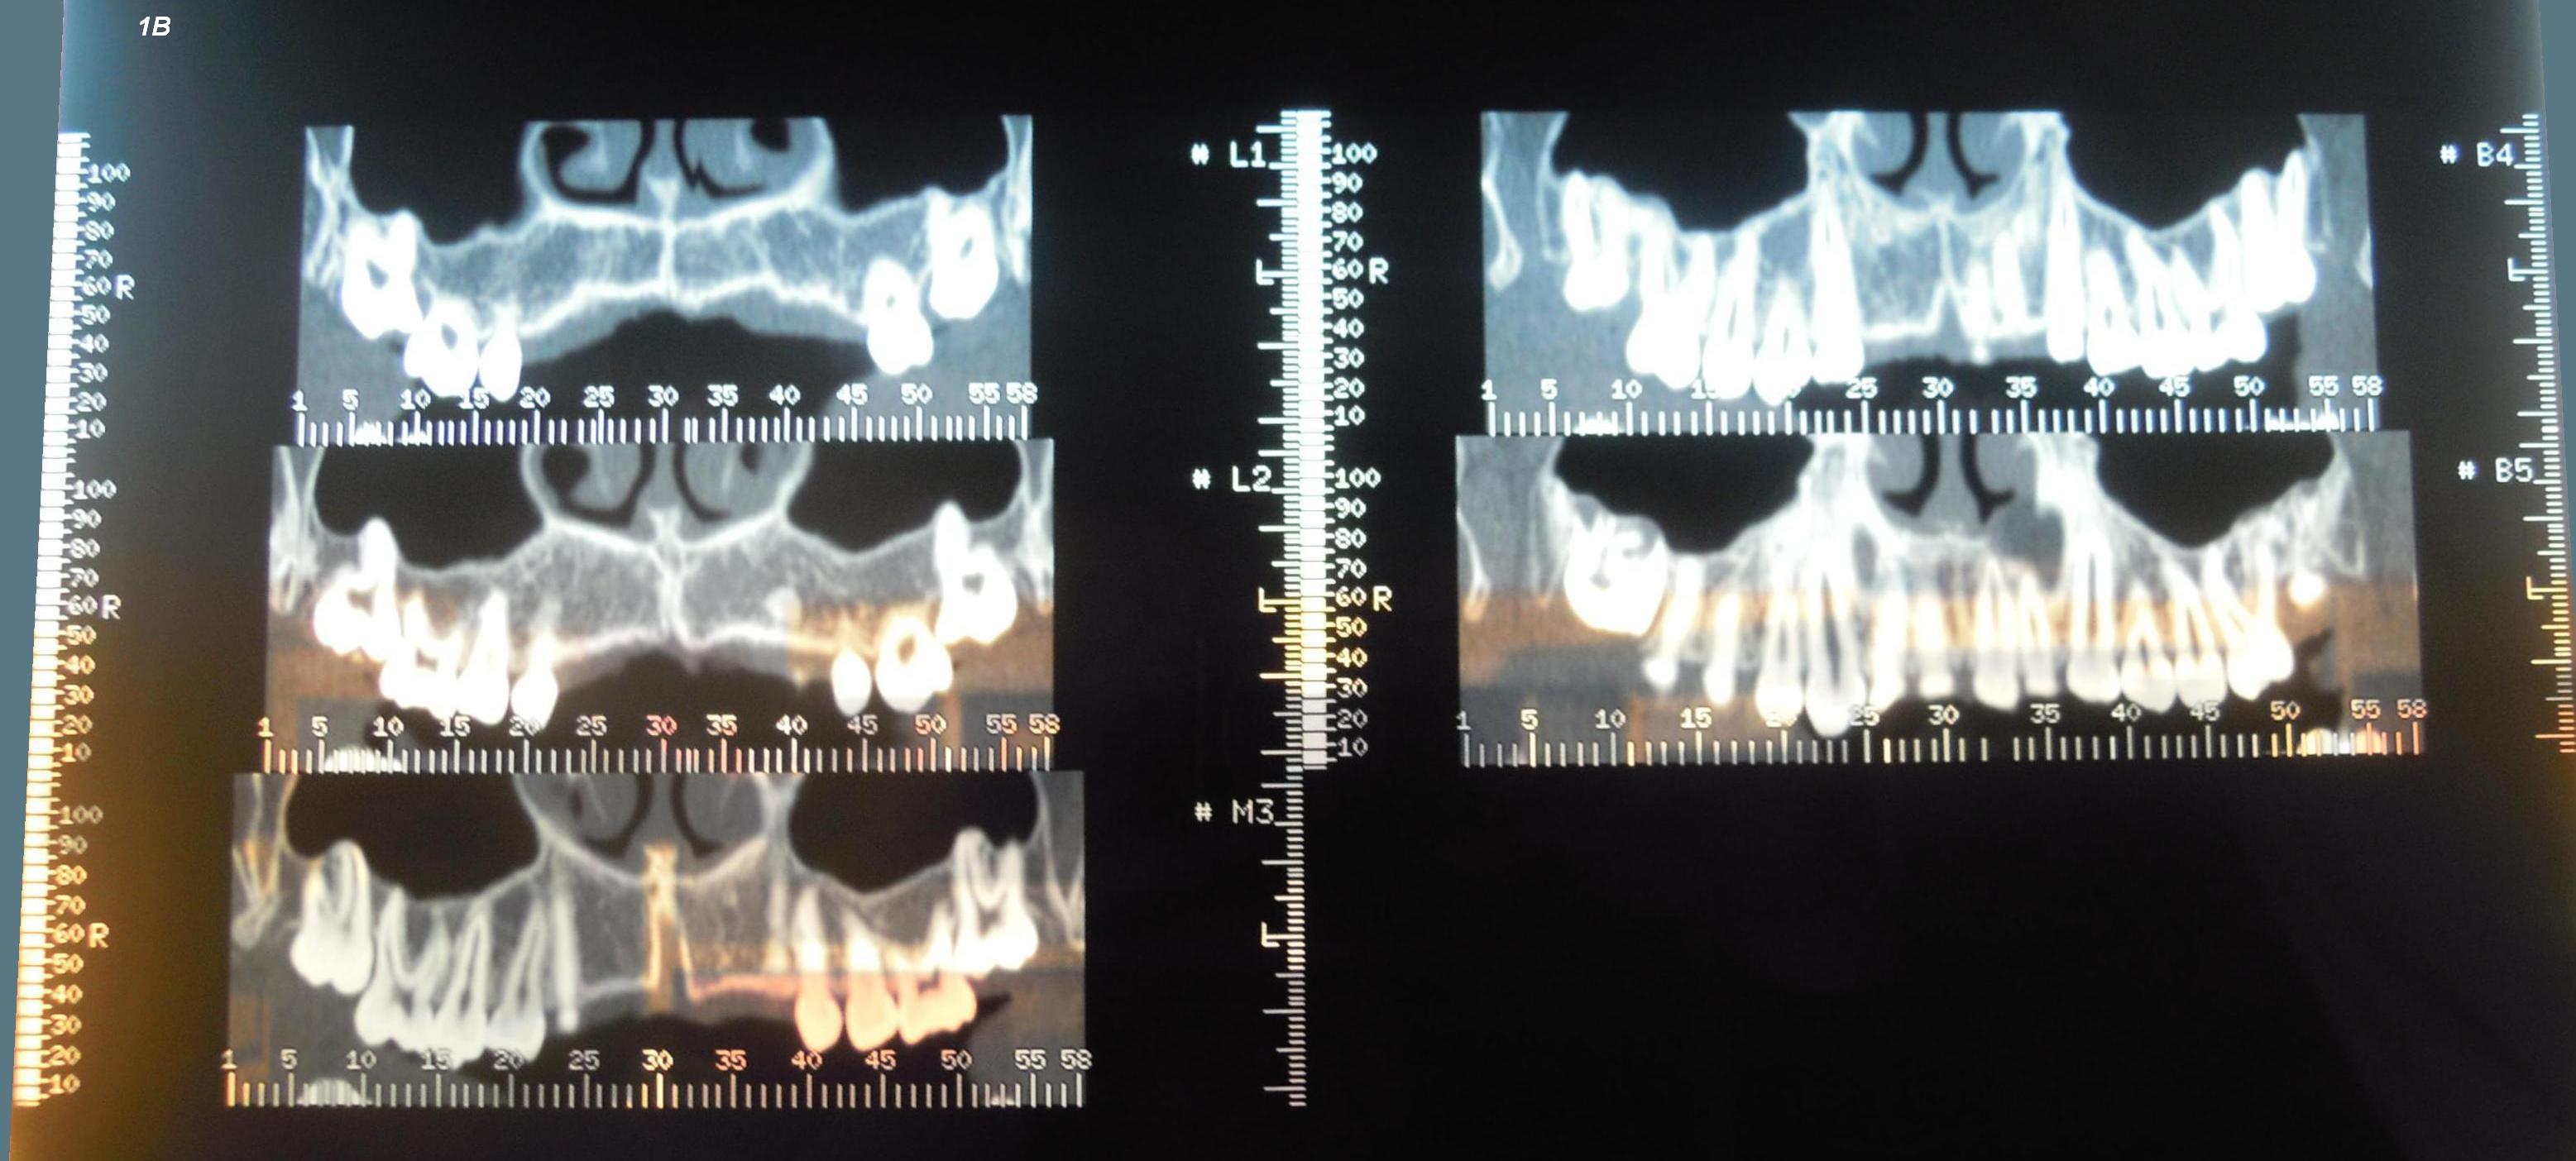

Salve, allego le immagini delle due lastre dental scan divise in 4 immagini per comodità, sarà un caso alla portata di tutti o ci vuole una notevole esperienza? cosa si evince da queste immagini, che quadro della situazione; qualcuno ha trattato con successo casi simili? Un parere, è mio figlio di 15 anni. GRAZIE

Caro Signor Domeniko, le ho risposto molto esaustivamente nientemeno che il 05-03-2012 ! Ma se lei non segue i consigli, personalmente non so più che fare. Le è stato consigliato di estrarre i denti del giudizio inferiore e quelli superiori scarcerando così i settimi, detto "a naso" e non certo dopo accurata ed indispensabile studio degli spazi clinicamente ed ortodonticamente, che o spontaneamente od ortodonticamente sarebbero erotto in occlusione. Questo perchè a limite si potrebbe fare il contrario a seconda della diagnosi ortodontica ottenuta col Ceck up e cefalometria, per esempio estraendo i settimi per riportare in occlusione invece gli ottavi!Le è stato spiegato che per fare questo sarebbe stata necessario fare una TAC dei denti che si chiama appunto CBCT, ossia Cone Beam Computer Tomography o anche CB3D, ossia Cone Beam tridimensionale, non certo per noi ma per il Dentista che avesse visto e preso in cura suo figlio. Le è stato spiegato che prima di fare tutto questo si sarebbero dovuti studiare gli spazi ed i rapporti dento dentali, dento scheletrici e scheletro scheletrici ortodonticamente con un Ceck up ortodontico ed una cefalometria che studia su una teleradiografia, su fotografie del profilo e frontali in rapporto 1:1 e modelli di studio e tanto altro, dei segmenti di retta ed angoli di punti di repere ben precisi per fare una diagnosi corretta! Non ha compreso tutto questo, mi spiace dirlo e che non si può valutare ed affrontare seriamente il caso di suo Figlio via web ma bisogna vederlo clinicamente e strumentalmente di persona! Quindi lo porti da un Dentista Ortodontista e lo faccia visitare. Lui deve vedere e leggere con suo figlio presente ed altre lastre in "mano" le lastre postate ora!Cordialmente Gustavo Petti, Parodontologia, Implantologia, Gnatologia e Riabilitazione Orale Completa in Casi Clinici Complessi ed Ortodonzia e Pedodonzia la figlia Claudia Petti, in Cagliari

Come le dicevo qualche giorno fa, bisogna valutare la questione da un punto di vista polidisciplinare. Diciamo così, senza assolutamente voler essere spocchioso in questo che dico, che è l'ortodontista che valuta la situazione nel suo complesso, dopo aver studiato a fondo l'occlusione ed il problema nella sua vera globalità, tramite l'effettuazione di una cefalometria o anche due in varie proiezioni. Ed è l'ortodontista che chiede al chirurgo (ed è a questi che servono le rx che lei ha fatto, non all'ortodontista che ha bisogno di un altro tipo di rx) di fare un intervento secondo quello che è un PROGETTO complessivo sulla situazione di crescita occlusale del bambino. Queste due figure possono naturalmente coesistere nello stesso professionista, oppure, più probabilmente NO: l'ortodontista deve essere un professionista di esperienza e generalmente il chirurgo è un mono specialista ospedaliero. Ma le realtà sono infinite e questa distinzione che ho fatto può essere addirittura stupida, giusto per farle capire meglio che PRIMA bisogna valutare il ragazzino dal punto di vista ortodontico, e POI fare estrazioni etc.

Gentile Sig. Domeniko, per avere un quadro più sicuro bisogna fare anche una cefalometria. La sola visione del dental scan non ci permette di suggerire una terapia. Cordiali saluti

Direi che c'è un po' di affollamento! E' necessario togliere gli ottavi o i sesti superiori. Le estrazioni non sono di per se un problema, ma il problema è capire cosa è meglio estrarre strategicamente per la soluzione del caso. Serve una visita di persona e una valutazione più completa.

Sig.Domeniko, chi ha prescritto questa TC le dovrà dar la corretta risposta, le ricordo che la TC non è indicata a scopo ortodontico.